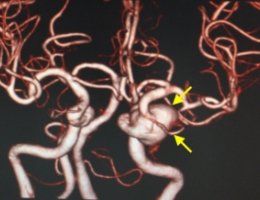

治療前

治療後

物が二重に見えるようになって発症した内頚動脈大型動脈瘤(矢印)の症例です。クリッピング術で直接動脈瘤をつぶすことができないため、バイパス術(矢印)を増設し内頚動脈を遮断することで動脈瘤を治療しました。